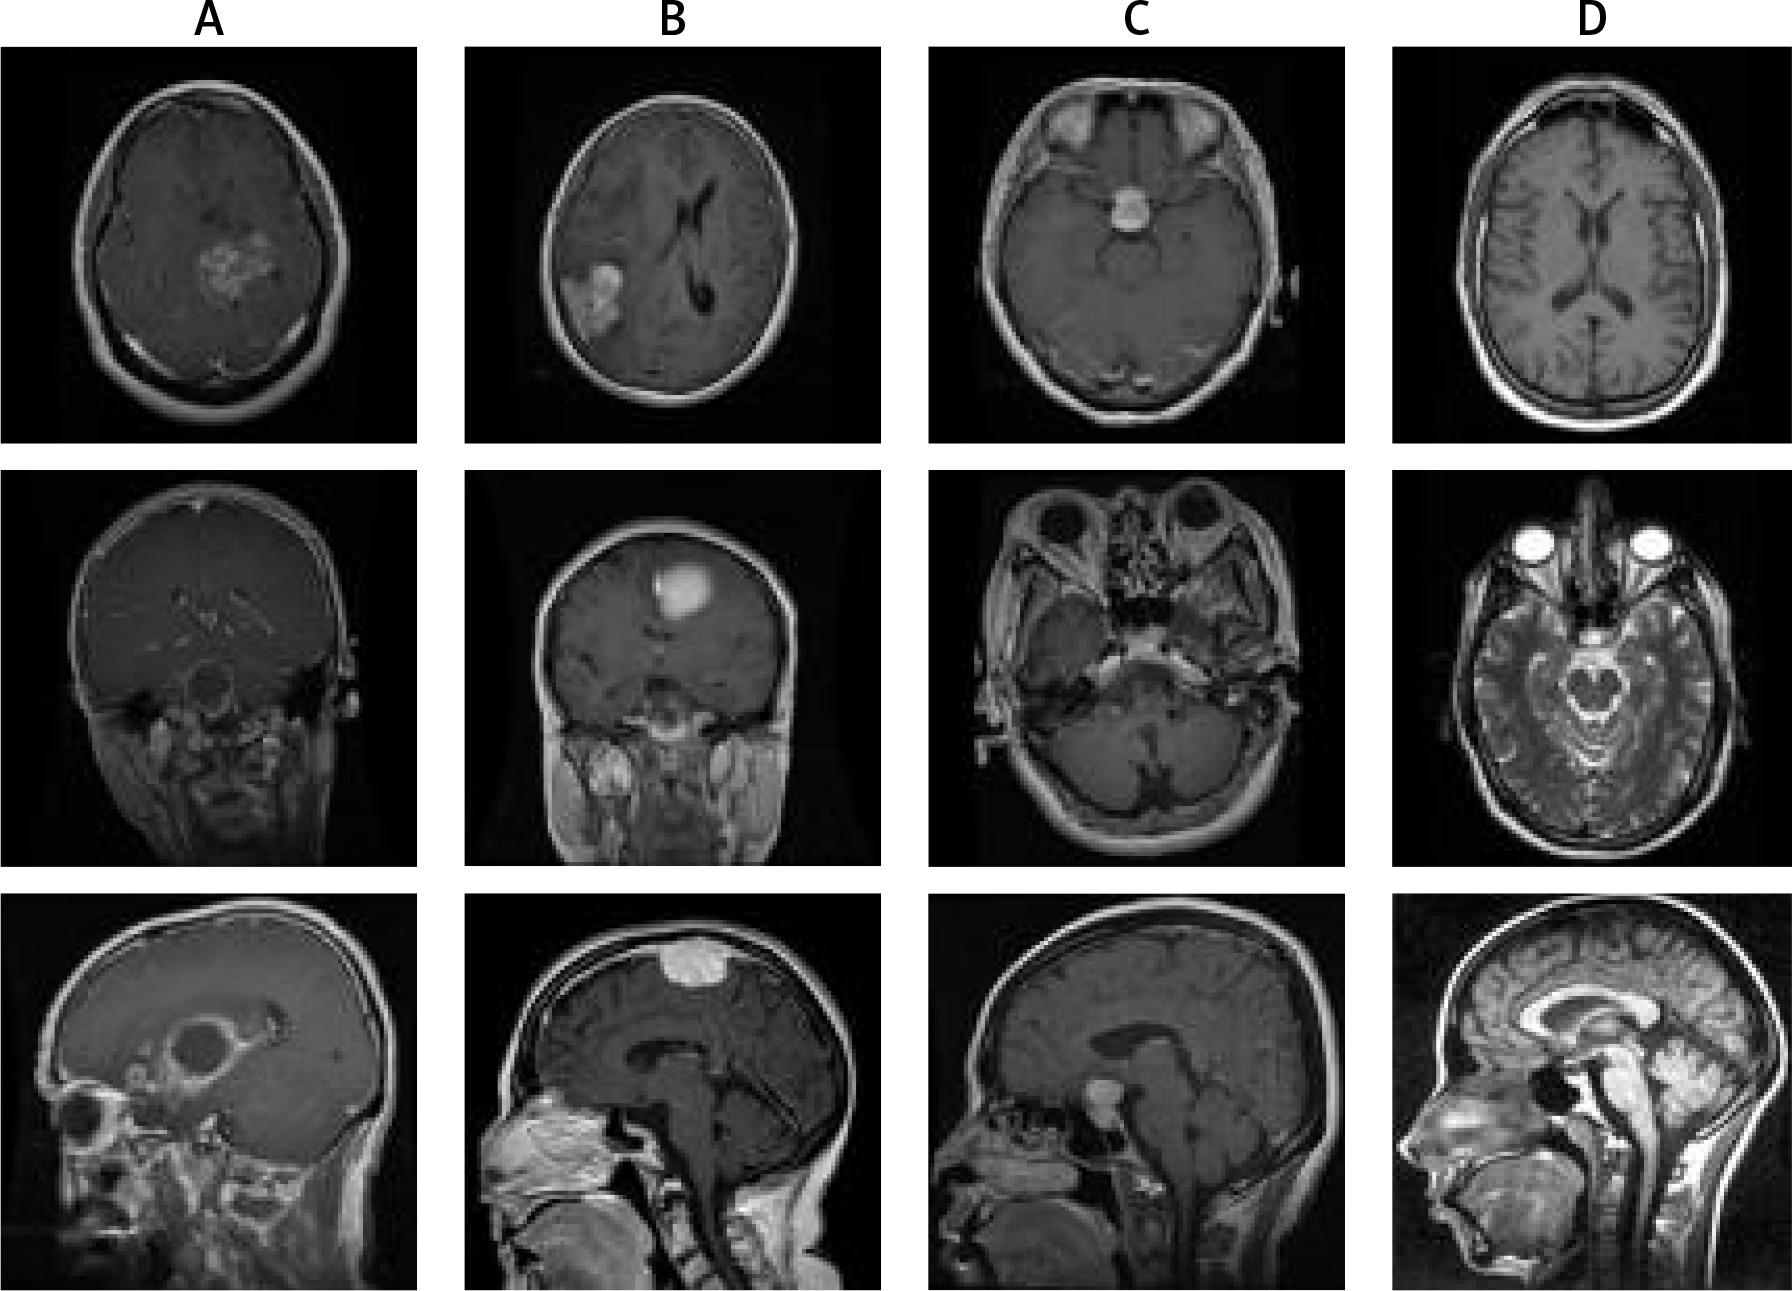

The brain dataset investigated in this study is collected from the Figshare repository [3]. The dataset comprises TI-weighted MRI of no tumour and 3 different types of tumours: meningioma, glioma, and pituitary. Image resolution of 512 × 512 with different views such as axial (transverse plane), coronal (frontal plane), or sagittal (lateral plane) planes was used in this dataset. The sample distribution based on the number of classes consisted of 826, 822, 827, and 395 sample instances of glioma, meningioma, pituitary, and no tumours, respectively. The sample of 3 types of brain tumour is shown in Figure 2.